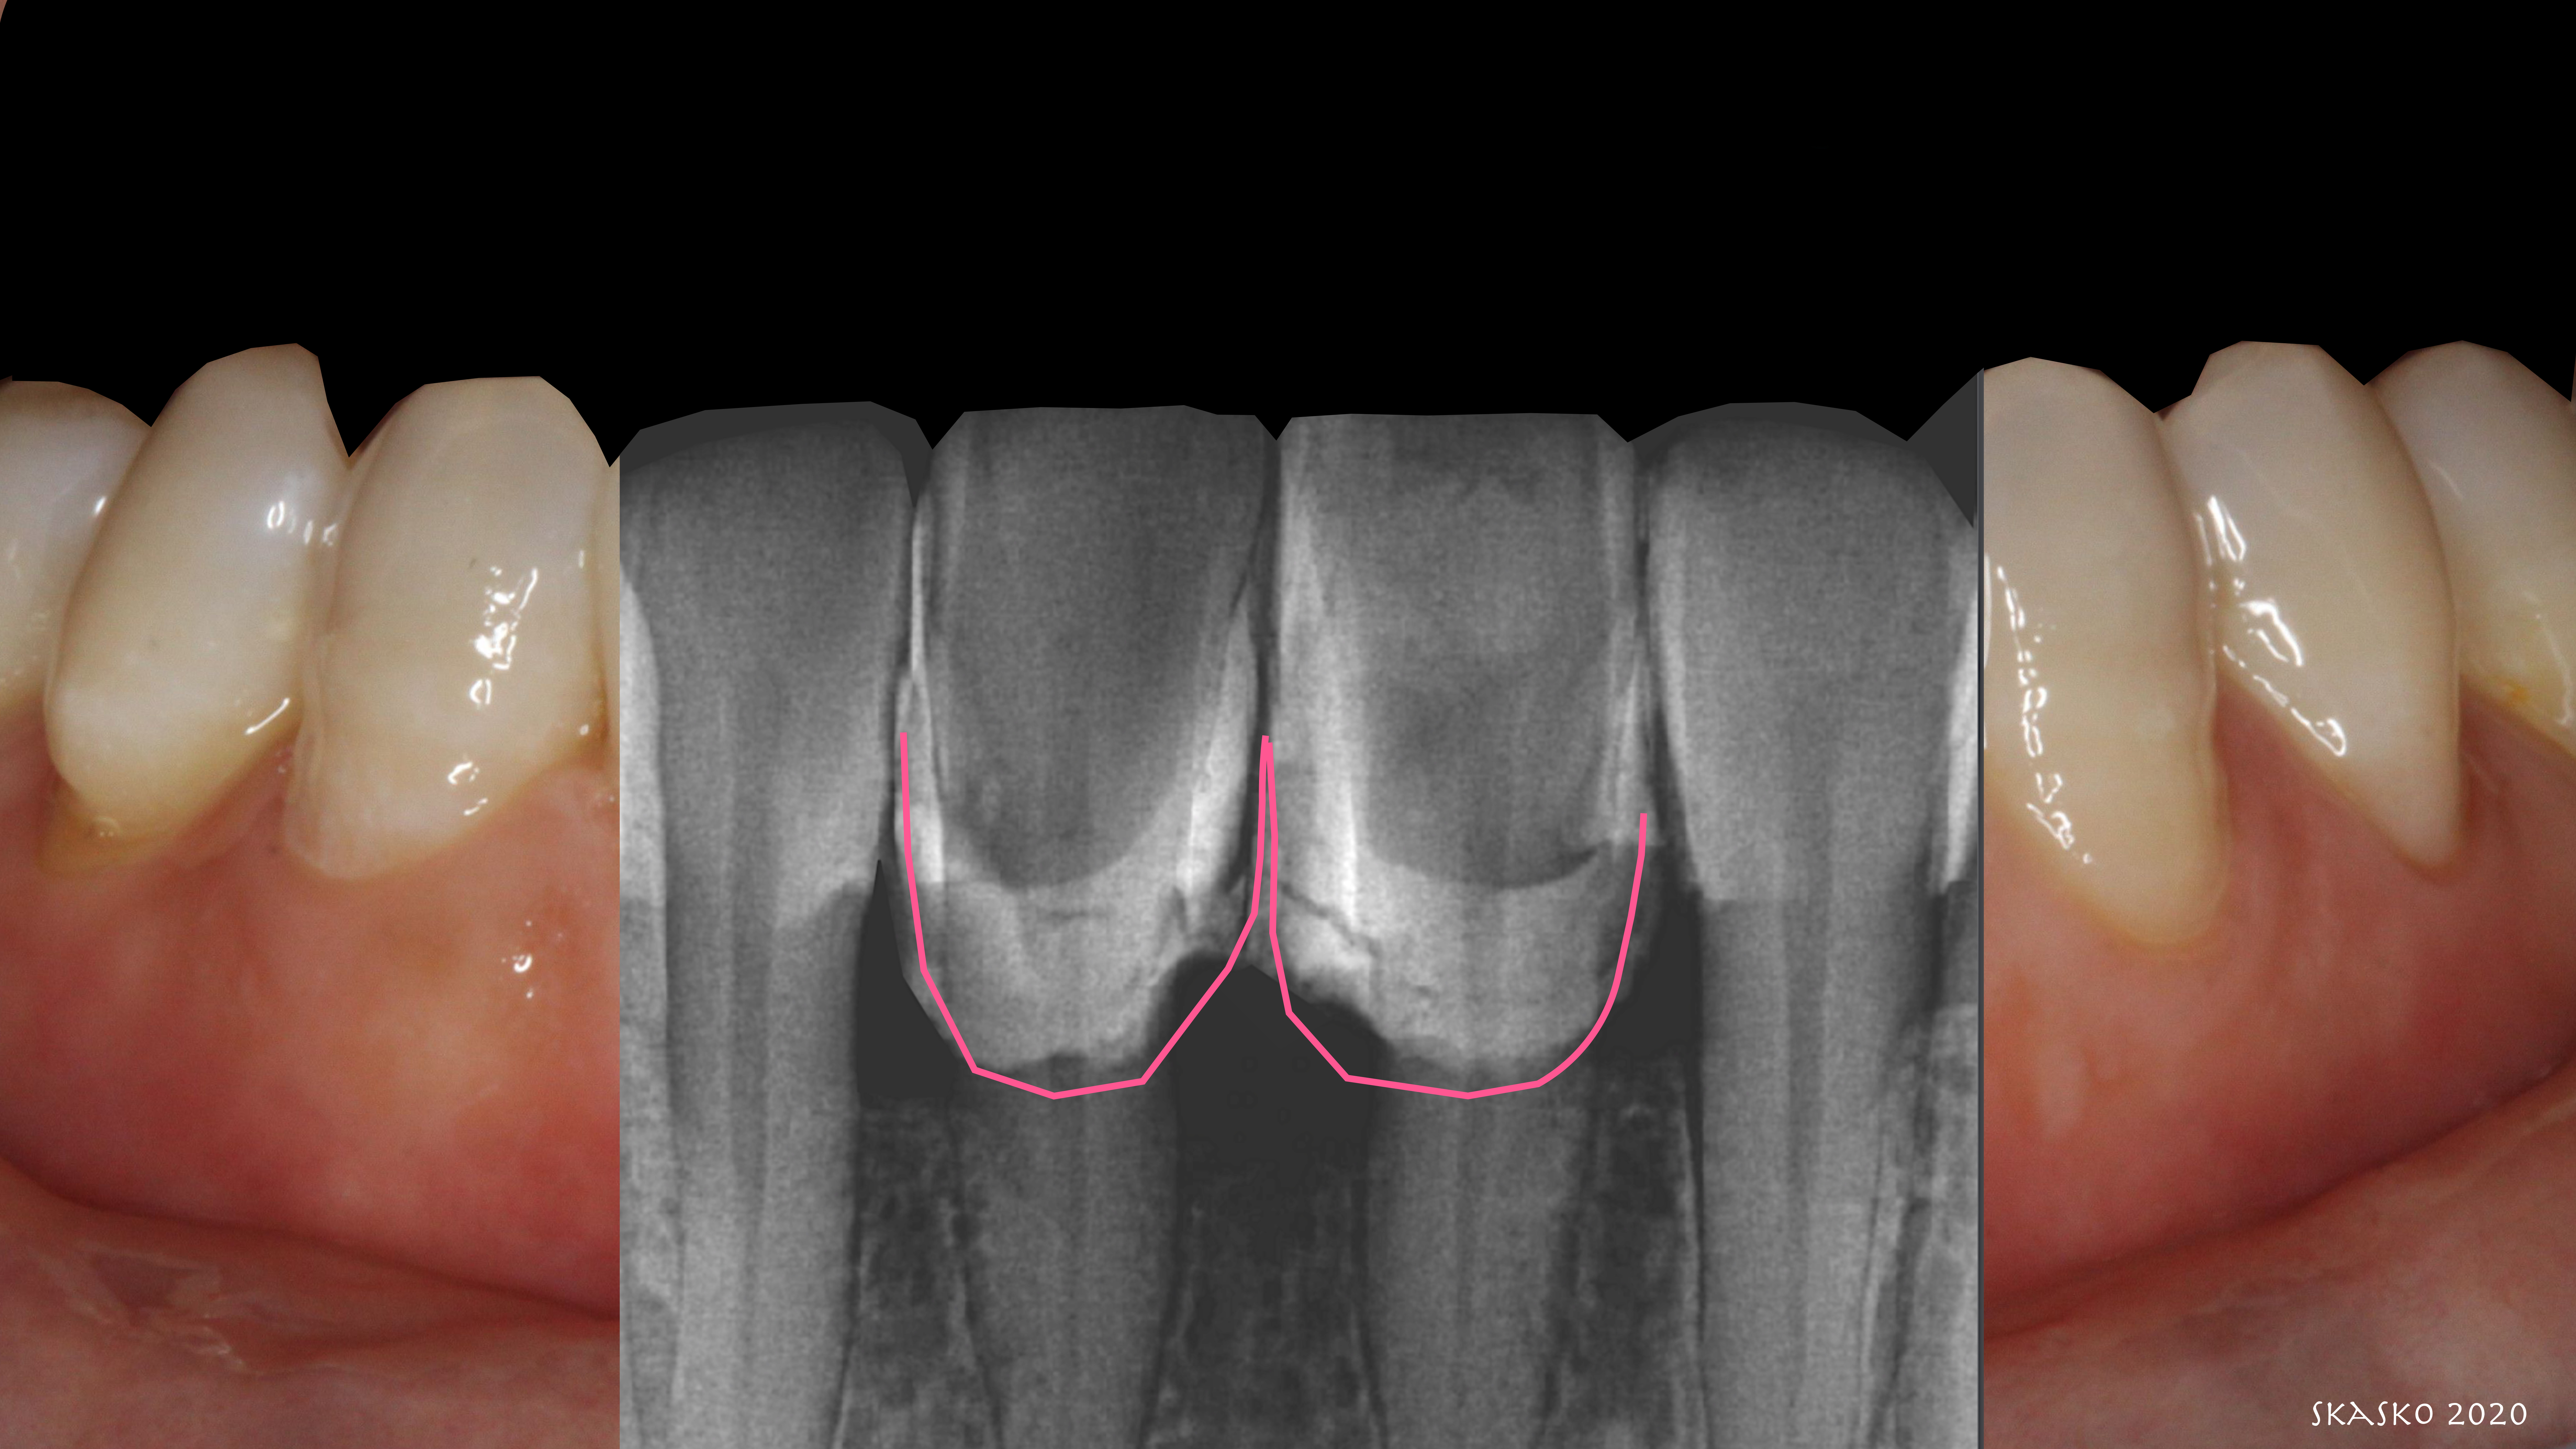

Composite bonding was the option chosen. The patient's teeth had some minor mobility, so the practitioner decided to tighten them via orthodontic arch wire splinting to hold them in place. They have done very well and now are not as mobile as before. See in the radiographic analysis where the pink and white is augmented (Figure 9). There were no issues with cleaning. Tissue healing was good. Practitioners must be very diligent about placing the materials and not leaving flash and excess.

Fig 9. Post-treatment radiographic analysis shows augmented pink and white.

Figure 9